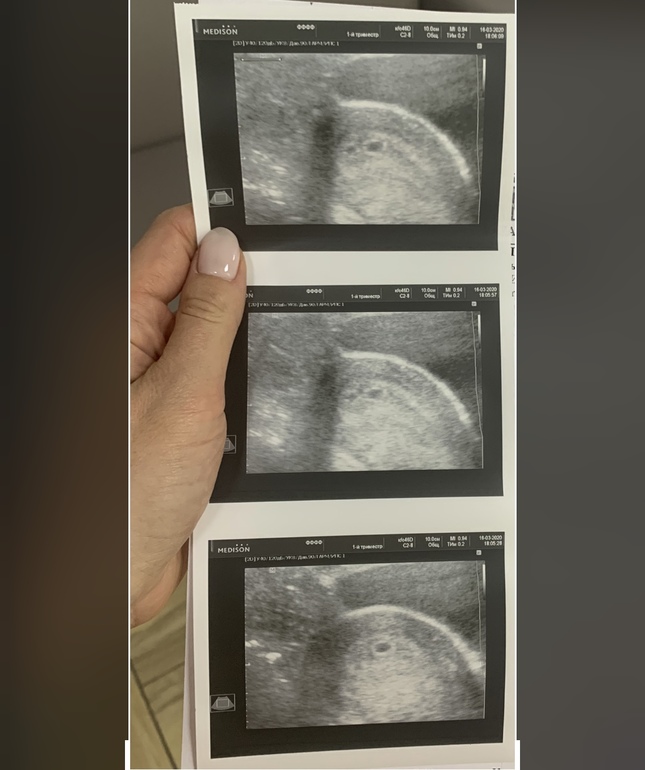

Подскажите, похоже на двойню 5 недель?

Кто сталкивался, или в курсе, или понимает. Сделали узи, сказали один Эмбрион видно, значит 1 ребёнок, но почему два кружочка на узи? Первая беременность

Очень маленький срок. У меня ди ди двойню увидели на 6 недель и 3 дня. ПЯ были одинакового размера.

Или микро миома какая нибудь или второе пя) повторите узи через пару дней-неделю)

Вообще интересненько, но качество очень плохое и точно сказать нельзя. Думаю врач бы обратила внимание, если бы подумала, что это второе плодное яйцо. В любом случае на повторном узи через дней 10 уже все будет ясно :)

Ну так и сказала, ,может двойня, а может и нет, и через 10 дней прийти. Но покой утерян)

Очень похоже, скорее всего двойня. У меня срок чуть меньше был, вообще было мало что понятно, но две точки увидели, врач думала или то или то, а оказалась двойня)